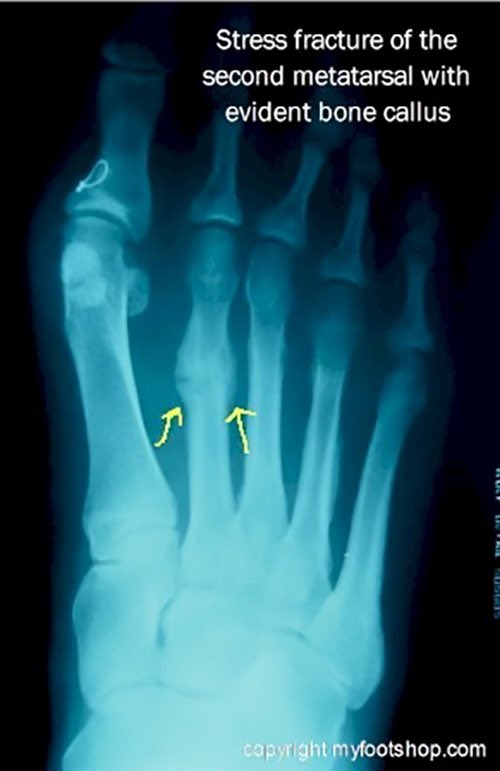

5-Repetitive microtrauma

وهذا يجيب لنا مايسمى بالشعر الي يجي من الضغط الزايد والاستخدام المتكرر والكرف بالعربي يسبب لنا fatigue fracture or stress fracture

اعرف اثنين عسكر بسبب لبس الحذاء غير المناسب والشغل الزايد صار عندهم كذا مع الوقت .